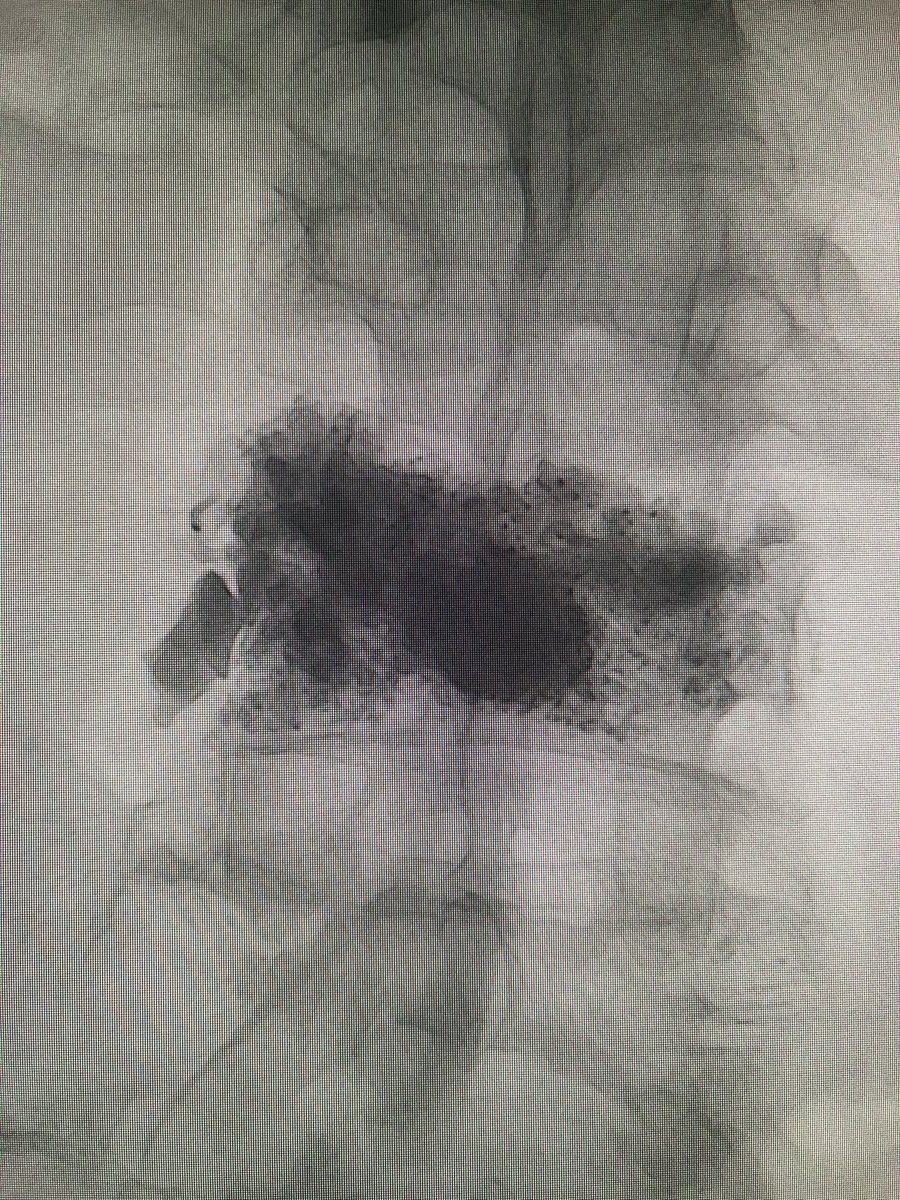

Excellent fill of the vertebral body with #KyphonVue! Only one way to truly celebrate such a good fill: #AirGuitar Thanks to @Coachkevin1026 for being the #BackupSinger

darthglader's tweet image. Excellent fill of the vertebral body with #KyphonVue! Only one way to truly celebrate such a good fill:

#AirGuitar

Thanks to @Coachkevin1026 for being the #BackupSinger